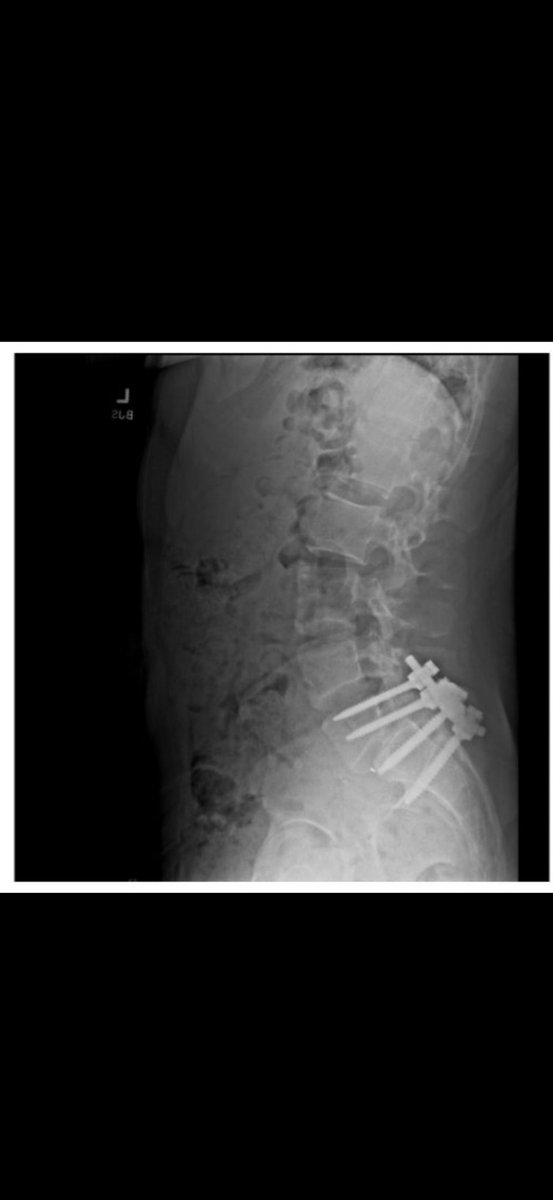

🚨🇺🇸 MANGIONE POSTED X-RAY IMAGE LINKED TO POSSIBLE MOTIVE, POLICE INVESTIGATE An X-ray shared on Luigi Mangione’s X account shows a spinal fusion surgery with screws and rods stabilizing the lumbar spine. According to @grok , this type of surgery is typically performed to treat trauma, deformities, or conditions like degenerative disc disease. Investigators are working to determine if the X-ray is Mangione’s or a relative’s and whether it connects to the killing of UnitedHealthcare CEO Brian Thompson. Friends have allegedly claimed Mangione “changed” after his surgery, a lead now under scrutiny. Source: Fox, X